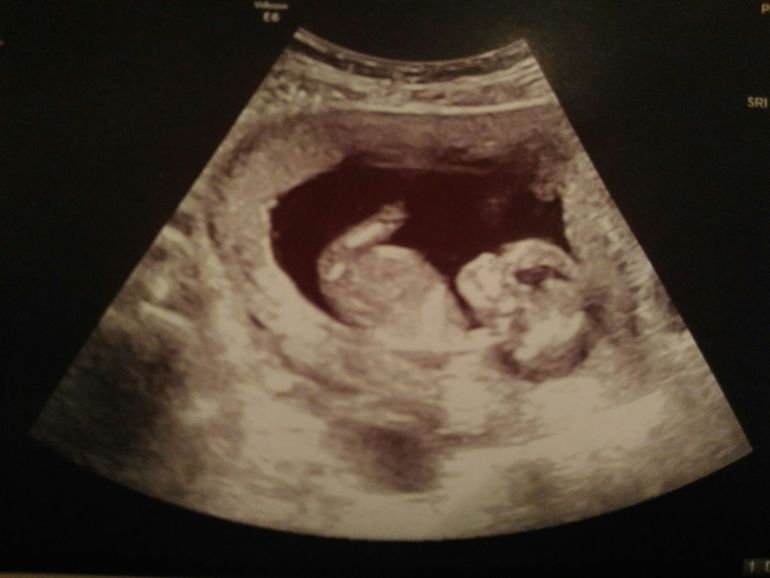

13 недель и первый скрининг

Всё о нашей беременностиСходила на первый скрининг.

Растет наша ягодка, уже 68 мм.

Как обычно крутился, вертелся, ногами и руками упирался в стенки плаценты.

Уже был виден желудочек крохотный, сердечко во всю бьется, пальчики на ногах и ручках.

Акушерка сделала все замеры: носик, шея... И сказала, что опережает в развитии на 1 день )))))))))

Акушерка предположила, что очень похож на мальчика, но пока точно сказать невозможно.